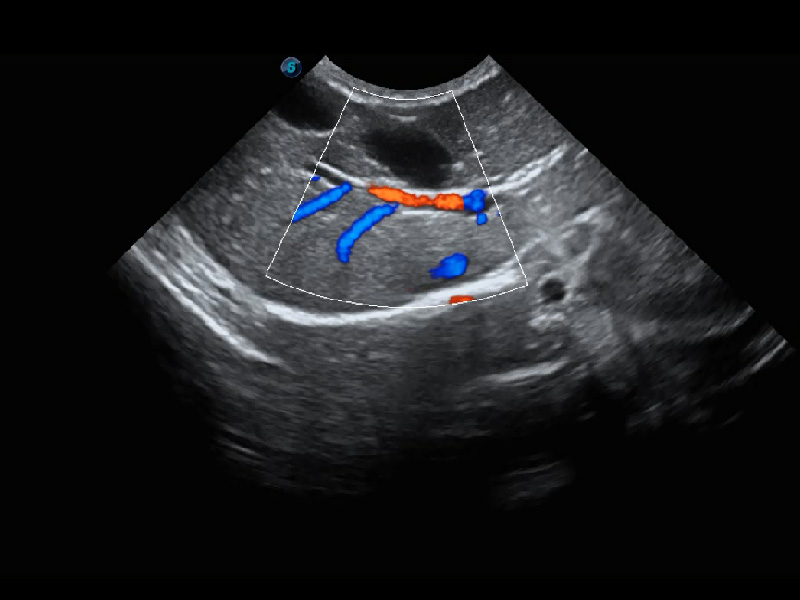

ProPet 60 作为一款高端台式动物超声设备,为动物医生的日常诊断提供了一系列贴合动物临床需求、解决临床实际问题的高级成像功能。凭借全系列高清探头,满足医生对腹部、心脏、生殖、浅表、肌骨等成像的所有需求,切实帮助您提升检查效率,提高诊断信心。

动物是人类最亲密的朋友和最值得信赖的伙伴。milan米兰也一直致力于探索动物专用的超声影像解决方案。 全新推出的ProPet系列,是milan米兰在动物超声影像智能化、专业化、精准化的一次跨越式革新。动物不能用言语来表述自己的不适,通过超声影像,ProPet系列搭建了动物医生与不同物种沟通的“桥梁”,为动物医生注入了“治愈之力”。